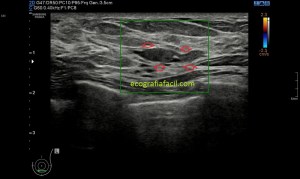

2

Eje largo, con la anatomía de referencia. Observamos las fibras alargadas, rodeadas por el líquido y el abombamiento producido por el sangrado.